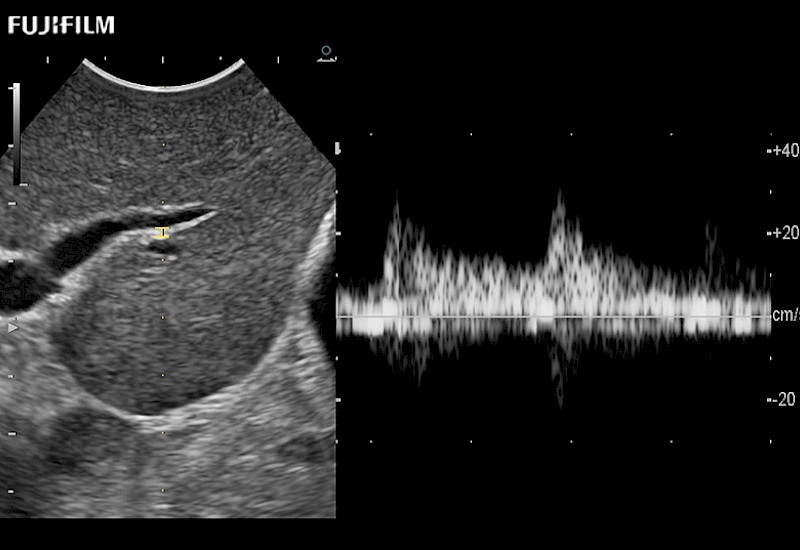

Learn moreFujifilm Healthcare continues to listen to the experts, our neurosurgeons, by developing an ultrasound system specifically designed for the Operating Room.

Guidance is the fundamental purpose for all of our surgical ultrasound technology. Fujifilm Healthcare is committed to designing tools that help neurosurgeons navigate inside the human body and provide the necessary information to immediately make critical surgical decisions.

With the ARIETTA Precision the next level of surgical ultrasound is here.